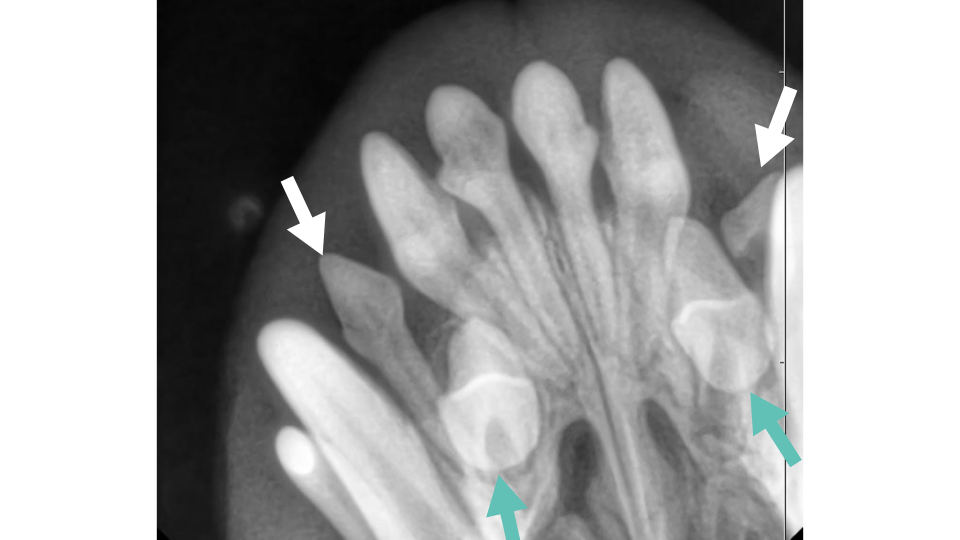

歯科レントゲンの所見がこちらです。

白矢印の乳歯の根本に、緑矢印で示した永久歯が埋まっています!

この症例は2歳でしたので、今後この埋伏歯が萌出することはおそらくないでしょう。

埋伏歯は放置すると6歳などの中年齢で歯肉が腫れてしまう含歯性嚢胞のリスクになります。

見つかった場合は基本的に抜歯処置が必要ですので、乳歯が残っている子や永久歯が足りない子は必ず歯科レントゲンを撮ってもらいましょう。